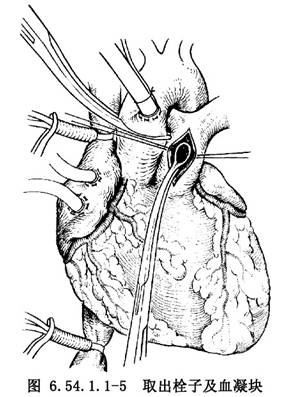

3.在肺动脉瓣环稍上方做肺动脉前壁纵行切口约2cm,牵开切口后以总胆管取石钳或小海绵钳伸入双侧肺动脉取出栓子及血凝块(图6.54.1.1-5)。